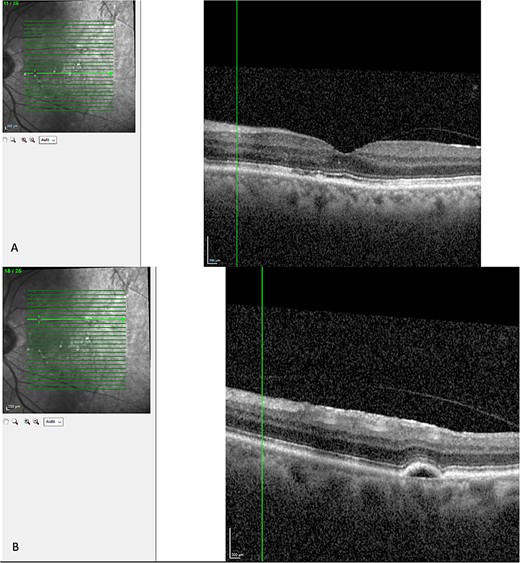

Finally, the patient was seen 12 months later. His left eye vision was 6/9 and his OCT showed a serous PED, with resolution of subretinal or intraretinal fluid as seen in Fig. 5.

Latest OCT of the patient’s macular. (A) Shows absence of intraretinal or subretinal fluid. (B) Shows a pigmental epithelial detachment.

Despite 9 months since cessation of steroid therapy, the patient had persistent left subretinal and intraretinal fluid and fluctuating corrected visual acuity ranging from 6/6-2 to 6/9. His ophthalmologist opted against invasive treatment as it was the patient’s better seeing eye. This was now called chronic CSCR, and the decision was made to monitor.

Although the patient’s subretinal and intraretinal fluid has resolved; It’s possible that he will have a recurrence of CSCR as a previous study found that 31% of patients had recurrence [7].